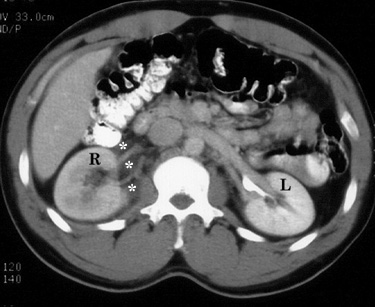

Figure 1. Contrast-enhanced CT image at the level of the kidneys shows delay in the right (R) nephrogram when compared to the left (L). Also note infiltration of the right perinephric fat (*). |